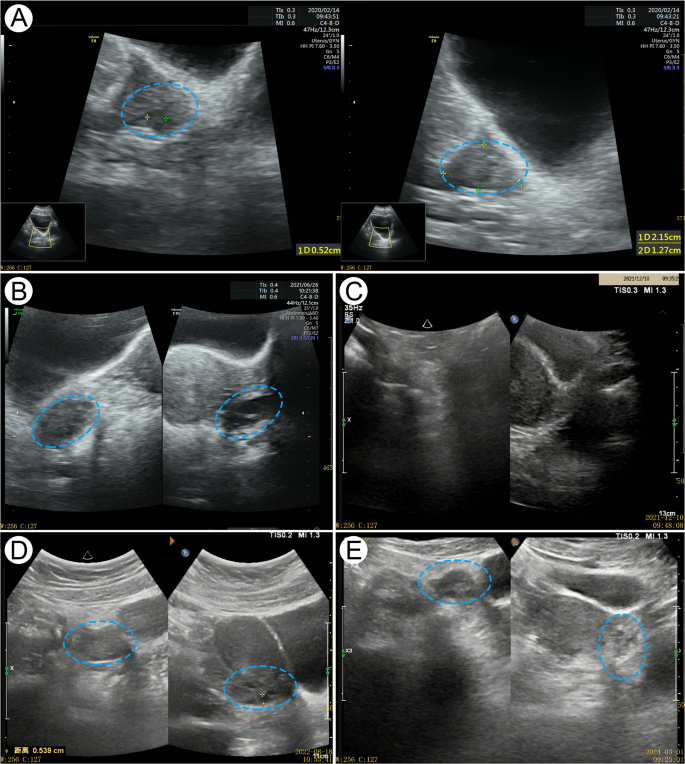

The changes of AMH, E2 and FSH levels, the changes of uterine adnexa and breast color ultrasound, and the results of liver and kidney function of patients at each time point are shown in Fig. 1; Table 1.

Ultrasound pictures of the patient’s ovarian. The blue frame indicates the changes in the patient’s ovaries: A Baseline (2020.02.14): Bilateral ovaries with few follicles (2–3 per side). B Before discontinuation of Heyan Kuntai capsule (HYKT) (2021.6.26): The right ovary measured 2.7 × 1.8 × 2.5 cm with 5–6 follicles (max 0.7 cm), and the left ovary measured 2.6 × 1.2 × 2.0 cm with 4–5 follicles (max 0.9 cm). C After discontinuation of HYKT (2021.12.10): Ovaries shrank with no visible follicles. D After adding HYKT (2022.8.18): Unilateral antral follicles and ovarian volume increased. E Final follow-up (2024.3.1): The right ovary (5–6 follicles, max 0.7 cm) and the left ovary (4–5 follicles, max 0.5 cm) were normal in size